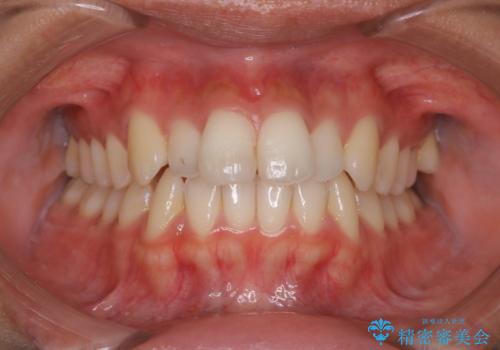

結婚式前の歯のクリーニング PMTC